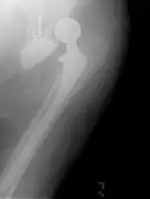

![]() تعویض مفصل ران راست با پروتز فلزی و کلاهک پلی اتیلن | |